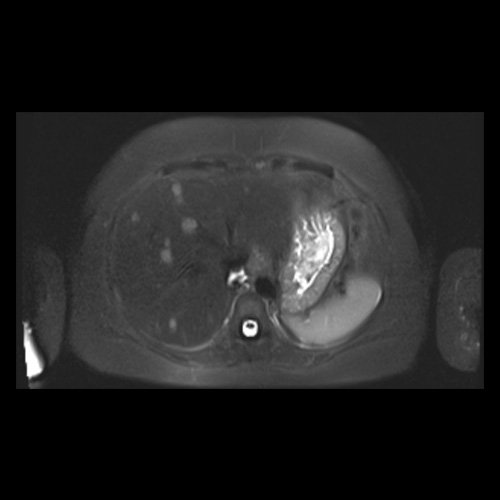

RMN de abdomen con contraste endovenoso (14/02/26) Corte axial (T2): múltiples lesiones sólidas de distribución difusa, levemente hiperintensas.

RMN de abdomen con contraste endovenoso (14/02/26) Corte coronal (T2): adenoma suprarrenal izquierdo; lesión hepática redondeada hiperintensa redondeada en segmento VII.

RMI abdomen y pelvis con contraste EV (14/02/26): En las bases pulmonares se visualizan atelectasias laminares bibalsales. No se identifica derrame pleural. El hígado es de forma, tamaño y situación normal. La superficie es lisa, los bordes son agudos. Se observan múltiples lesiones sólidas de distribución difusa, levemente hiperintensas en T2, con restricción en difusión y realce homogéneo tras la administración de contraste EV, la de mayor tamaño de 15 mm en segmento VII. Sugiero conocimiento histológico. La vía biliar intra y extrahepática es de calibre conservado. La vesícula biliar es de forma y situación habitual, sus paredes son finas y no presenta imágenes hipointensas en su interior, que sugieran la presencia de litiasis. El bazo es de forma, tamaño y situación normal, sin efectos de masa focales. El páncreas es de forma, tamaño y situación normal, sin efectos de masa. El Wirsung es de calibre conservado. Glándulas adrenales de forma, tamaño y situación normal, sin efectos de masa. Ambos riñones son de forma, tamaño y situación normal, con adecuada diferenciación córtico subcortical. No se observan alteraciones a nivel de la vía excretora. No se observan adenomegalias retroperitoneales ni intraperitoneales. La aorta abdominal, las arterias iliacas primițivas, internas, externas y femorales son de trayecto y calibre normal La vena cava inferior, las venas ilíacas primitivas, internas, externas y femorales son de trayecto y calibre normal. No impresionan alteraciones a nivel del tracto gastrointestinal. La vejiga es de paredes finas, normalmente distensibles, sin evidencia de lesiones endoluminales ni parietales. Mioma transmural en hoja anterior de útero que mide 55 x 47 mm sin signos de complicaciones. Imagen ovalada de contenido líquido que mide 65 x 52 mm en el espesor del tejido celular subcutáneo de región antero-superior de muslo derecho, por delante de músculo sartorio, que no presenta realce tras la administración de contraste EV.